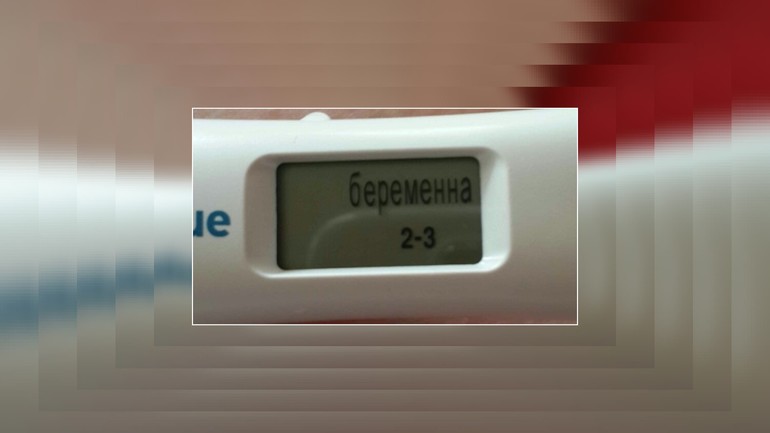

Мне узист сказала, что надо делать разных фирм тесты. И еще сказала что клеаблю не рекомендует. Я брала тест электронный с неделями показывает.